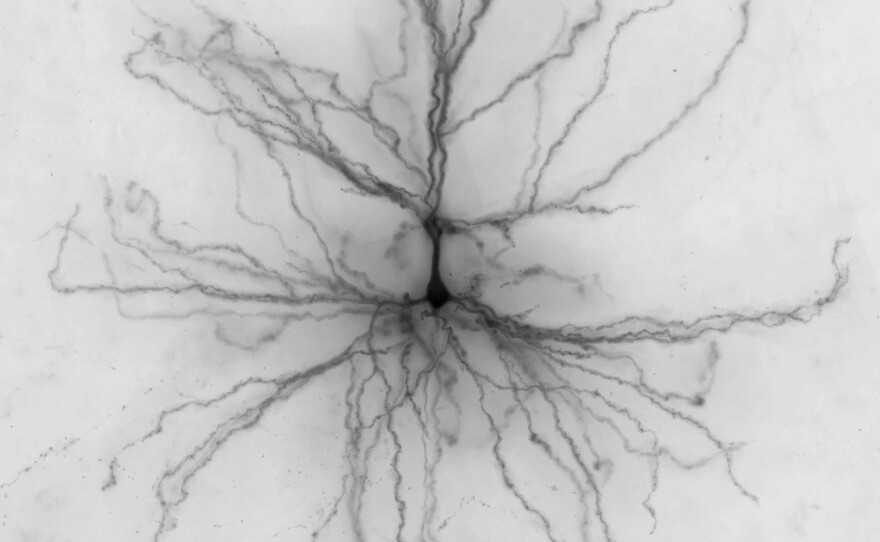

The virtual cells, unveiled Wednesday by The Allen Institute for Brain Science, capture not only the shape and anatomy of living cells, but also the electrical signals they produce.

Those signals, as well as data about each cell's physical structure, are captured in digital form and added to The Allen Cell Types Database, which is available to anyone with an internet connection.

So far, the institute has captured electrical data from 300 living neurons taken from the brains of 36 different patients. There are 3-D reconstructions for 100 cells. Ultimately, the institute plans to add genetic information about some of the cells.